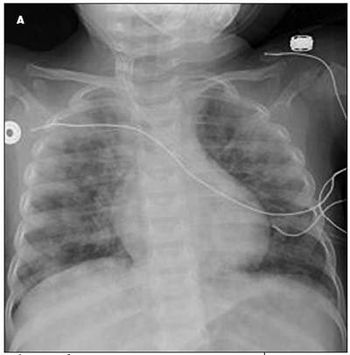

A 16-month-old girl was initially brought to her primary care physician because of persistent nonproductive cough of 1 to 2 weeks’ duration, with lethargy, poor feeding, and worsening cough for the past 36 hours. She had been afebrile. The patient was noted to be pale and had a decreased level of interaction. She was promptly sent to the local emergency department. Laboratory studies showed a hemoglobin level of 3.8 g/dL and hypochromic microcytic anemia. The patient was subsequently transferred to the pediatric ICU for evaluation.